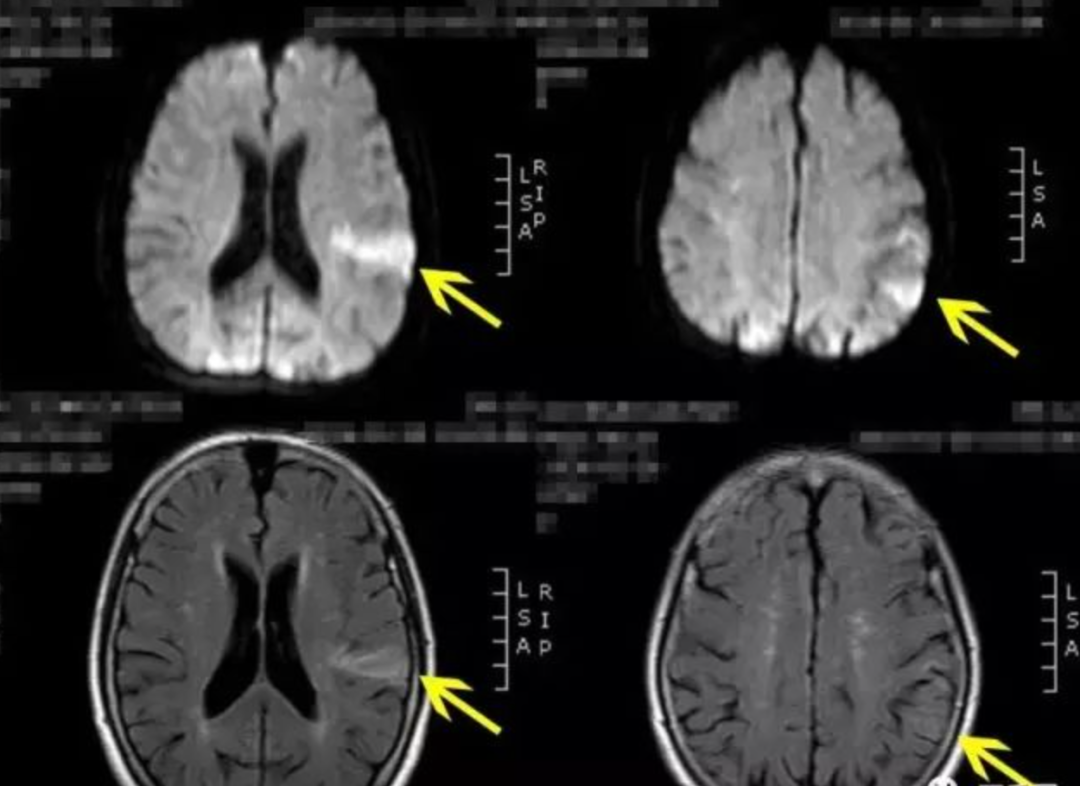

黄一宁教授对该病人的大脑做了MRI(磁共振成像),发现病人的颞叶,存在明显的缺血病灶,翻译成人话来说就是:病人大脑的颞叶区,发生了局部脑梗,导致脑功能失常,以至于产生了幻视。

如图,“见鬼”患者颞叶可见明显缺血病灶,简单地说,就是局部脑梗,导致出现幻视